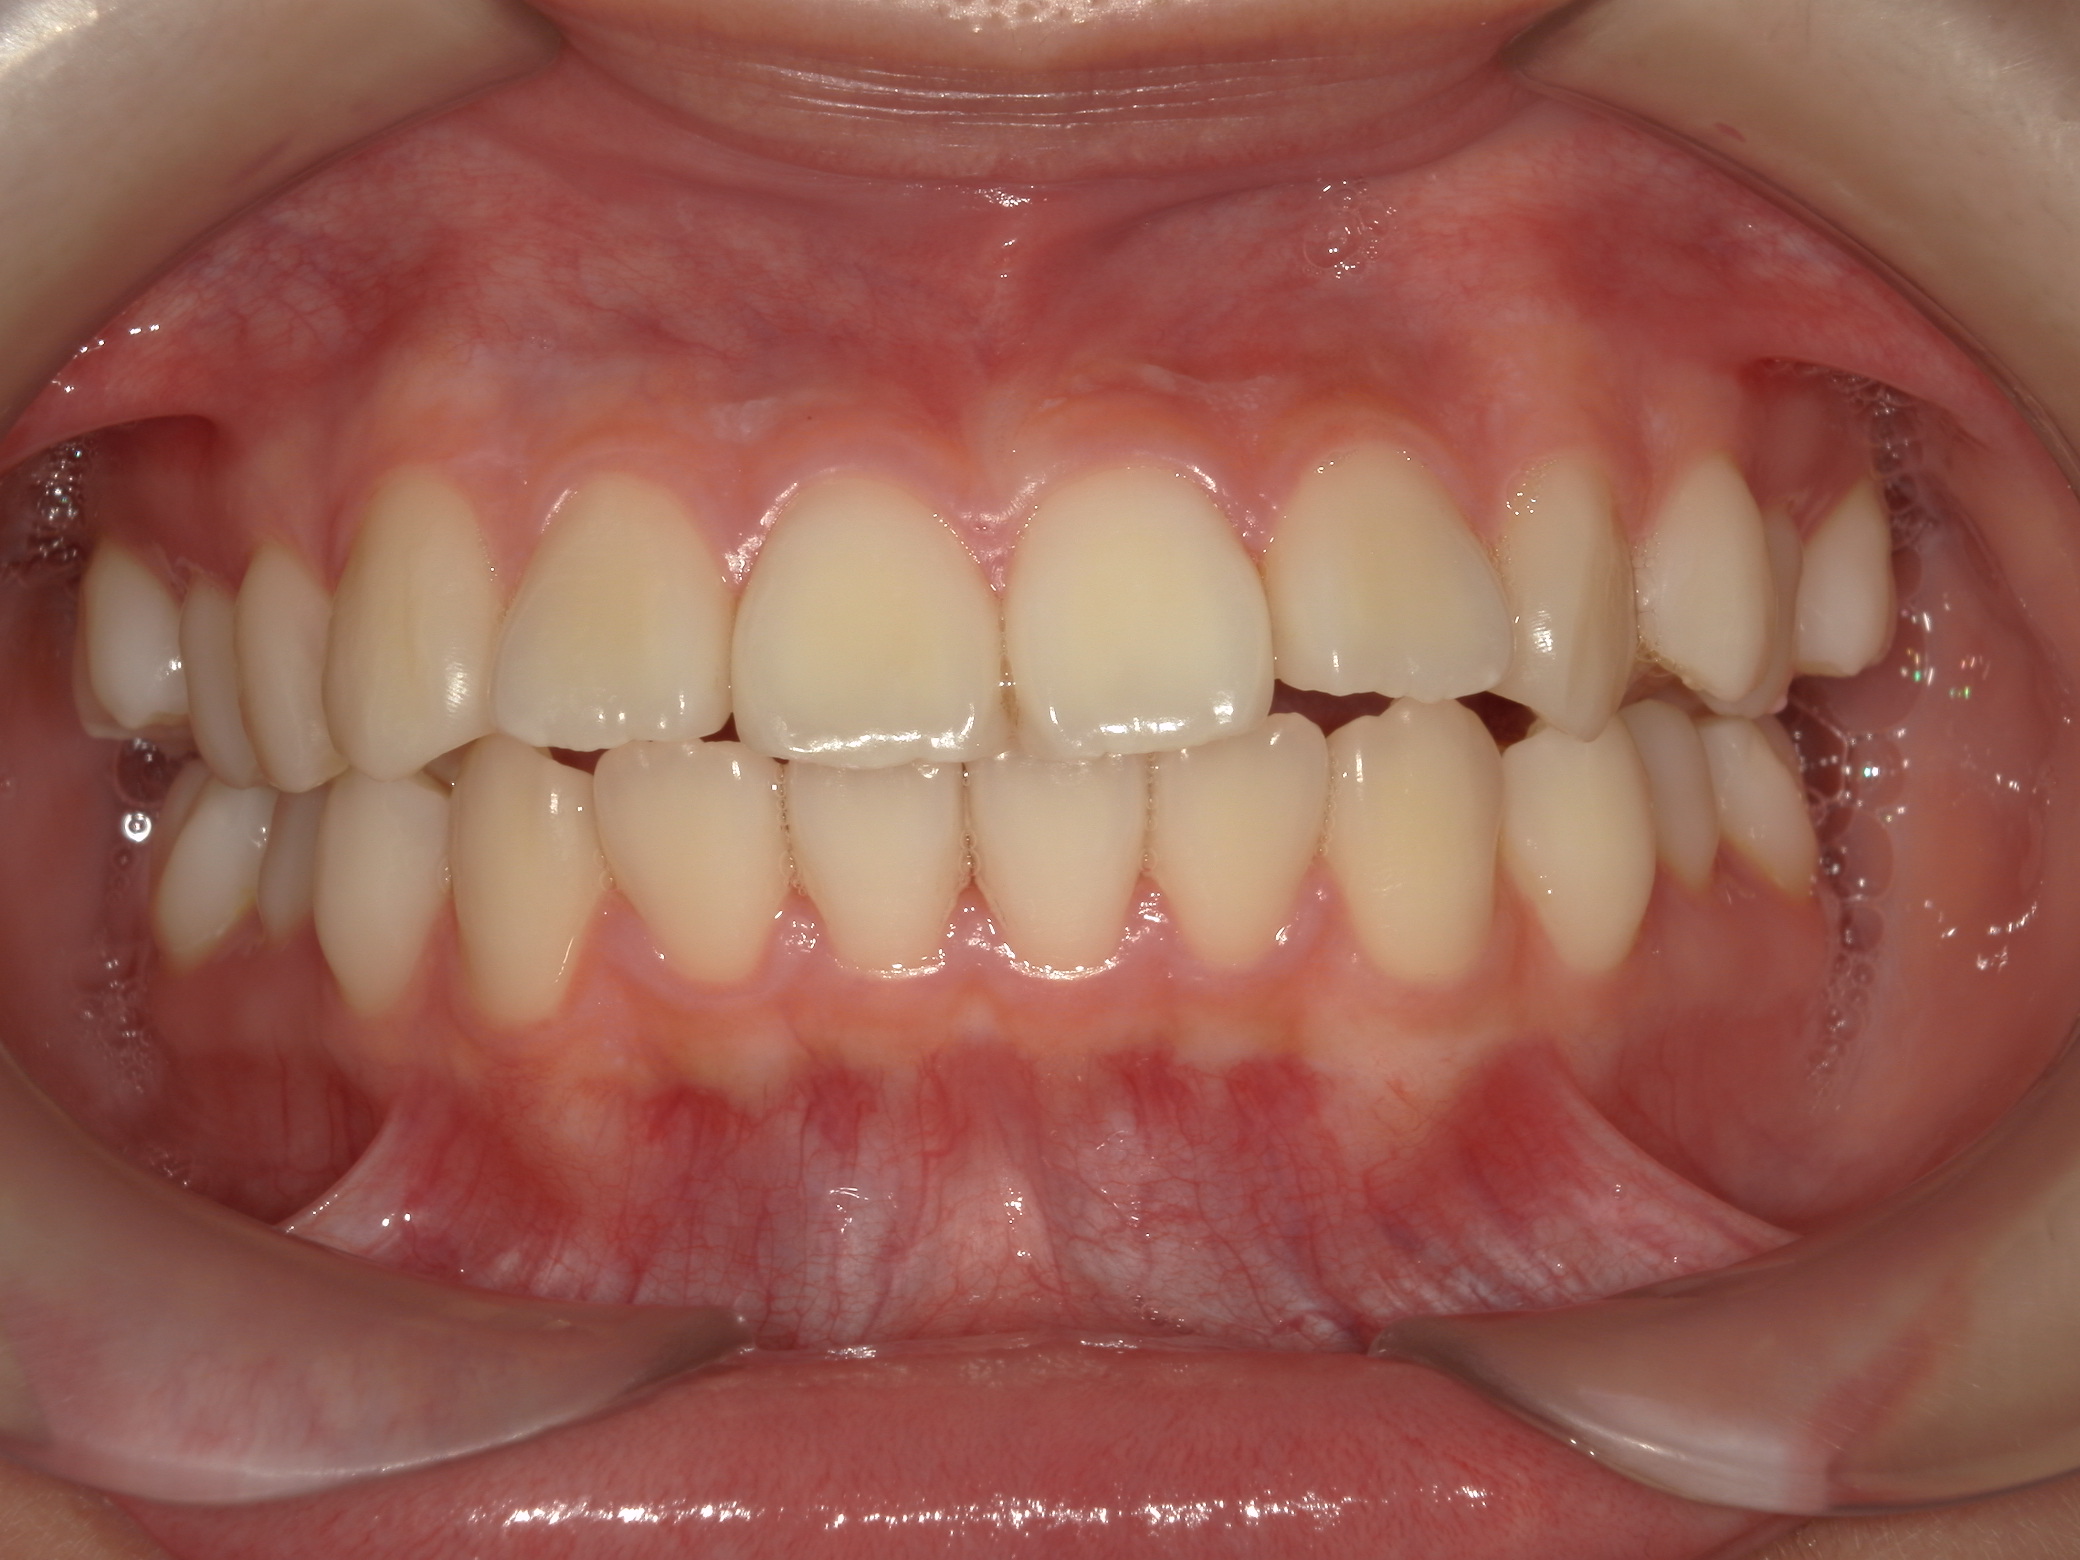

非抜歯拡大矯正(床矯正)の犠牲者が来院

中学3年の女の子が母親と同伴で矯正の相談に当院へ来院しました。

小学1年から中学1年まで床矯正した。中1でこれ以上できないからと他院へ紹介された。紹介先の歯科医院の日矯認定医に『酷いね。』と言われた。 初見で私も酷い矯正だと思いました。ですが、

通常12歳前後に始め目治療期間は2年前後で終わります。この症例の様に小学1年から6年越える期間、拡大しても結局抜歯しての矯正となった場合、抜歯前の矯正は全くの無駄です。意味がありません。6年続けたことで患者と保護者の精神的苦痛、時間の浪費、金銭の無駄は本当にお気の毒です。

この症例の気になるの点として、無理な拡大で下顎左右6番の歯根が頬側の皮質骨からはみ出ている危険があることです。そうならば、下顎6番の近心移動はものすごく遅くなります。等と考えていたので、当然のごとく抜歯部位の選定に悩みました。悩んだ末、この症例は上下左右の6番抜歯症例です。

口元がすごく出ています。